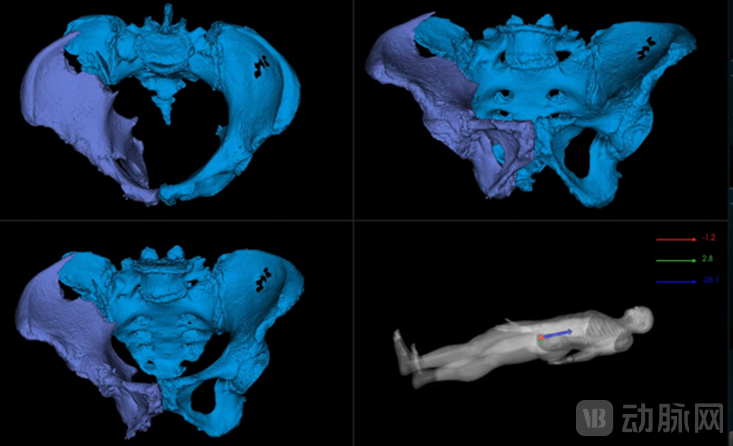

图为罗森万相®智能化骨科机器人系统

利用计算机自动规划以及主刀医师术中判断,实现了复位和内固定的自动手术规划提升骨科手术机器人智能化程度。

通过术前CT与术中影像的配准,首次实现对于骨折手术的三维导航,全面提升骨折手术的精度和安全性。

精确实施复位规划结果,计算复位路径,降低复位负载需求,复位操作误差<2mm。

术前无创,毫米级术中跟踪误差,毫秒级跟踪延时,三维模型及任意方向的CT层切。